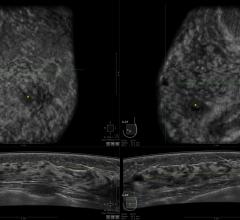

Women's health related to breast imaging, including mammography, breast MRI, ABUS, automated breast ultrasound, breast ultrasound, breast biopsy, PEM and positron emission mammography.

Despite decades of progress in breast imaging, one challenge continues to test even the most skilled radiologists ...

The U.S. Food and Drug Administration (FDA) reports digital mammography systems have largely replaced screen-film ...